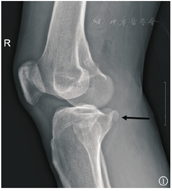

病例1 患者男,52岁,因"机器压伤致左大腿、右膝疼痛活动受限12 h"于2018年1月入院。入院查体:左侧大腿肿胀压痛,畸形,右膝关节肿胀压痛,活动受限,双下肢肢端血供感觉正常,由于疼痛查体欠配合。入院完善左侧股骨正侧位X线、右膝X线(图1)、CT(图2)及MRI(图3),诊断"左侧股骨干骨折、右侧反式Segond骨折"。为控制创伤,行分期手术。入院7 d后患者一期行"左侧股骨干骨折切复内固定术",术后恢复可。入院14 d行右膝关节镜辅助下内固定手术。麻醉下查体提示右膝关节30°外翻试验阳性,前后抽屉及Lachman试验阴性,术中常规行关节内血肿清理后发现前后交叉韧带无损伤,内侧半月板(medial meniscus,MM)撕裂予半月板成形,内侧撕脱骨折位于内侧半月板后角下方并向内侧移位,关节镜监视下克氏针体外定位骨折位置后取膝关节内侧2 cm切口纵行劈开内侧副韧带分离至骨折处,见骨折块约1.5 cm×1 cm×1 cm大小并翻转,在关节镜监视下复位骨折后用2枚3 mm空心钉固定,再可吸收线连续缝合修补内侧副韧带(medial collateral ligament,MCL),术后复查右膝X线(图4)示骨折解剖复位。术后常规佩戴可调节膝关节支具伸直位固定并行直腿抬高锻炼股四头肌,术后4周开始膝关节0°~90°屈曲活动,术后6周膝关节0°~120°屈曲活动并拄双拐保护下开始部分负重,术后10周膝关节完全负重并达到正常活动度。目前术后半年,查外翻试验转阴,日常生活无不适,能慢跑,打羽毛球,右膝无不稳感,Lysholm评分90分。

反式Segond骨折位于胫骨平台的内缘,因此在标准的膝关节X线正侧位片上容易漏诊,而斜位X线片上可以更好地显示该骨折。由于此类骨折常常合并膝关节韧带、半月板损伤,所以需要CT、MRI等影像检查进一步评估其他伴随软组织损伤,一旦漏诊可能会对治疗效果产生不利影响。